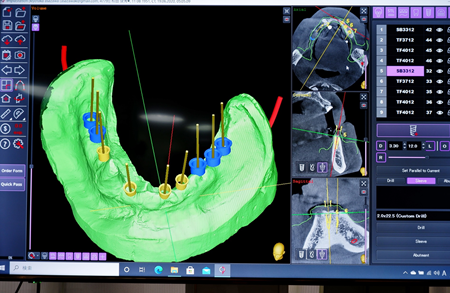

・あさざわ歯科医院では、歯科用CTスキャンを導入後、

コンピュータシュミレーションによって精密に製作されたガイデッドサージェリーでのインプラント手術を行っております。

| 【治療内容】 | 下顎はインプラントフルブリッジ、噛み合せが反対咬合、右側にずれる「かみ癖」のため、上顎はインプラント4本のオーバーデンチャー( 磁性アタッチメント義歯 )下顎は残存歯が1歯の多数歯欠損で手術用ガイドの固定源確保が困難でありましたが、インプラントをCTスキャンデータで作製した手術用ガイドを用いて9本埋入し、固定式3本連結のブリッジを3装置としました。